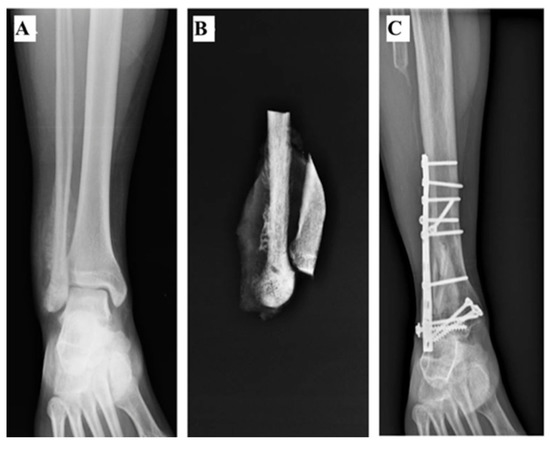

2.3. Non-Vascularized Fibula Transposition

| 5 | 95 | 11.1 | No | Yes (periosteal) | Yes | No | 0 | FT | 12 | Chronic pain | No | 29 |

| 6 | 118 | 16.5 | Yes | No | Yes | No | 2 | FT | 12 | - | No | 21 |